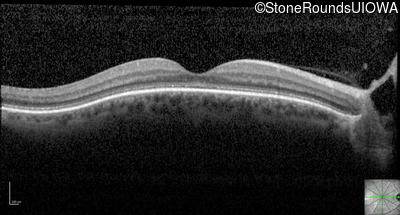

Optical Coherence Tomography - Left - 20/400 sc

Exemplar / OCT Stack

OCT Stack